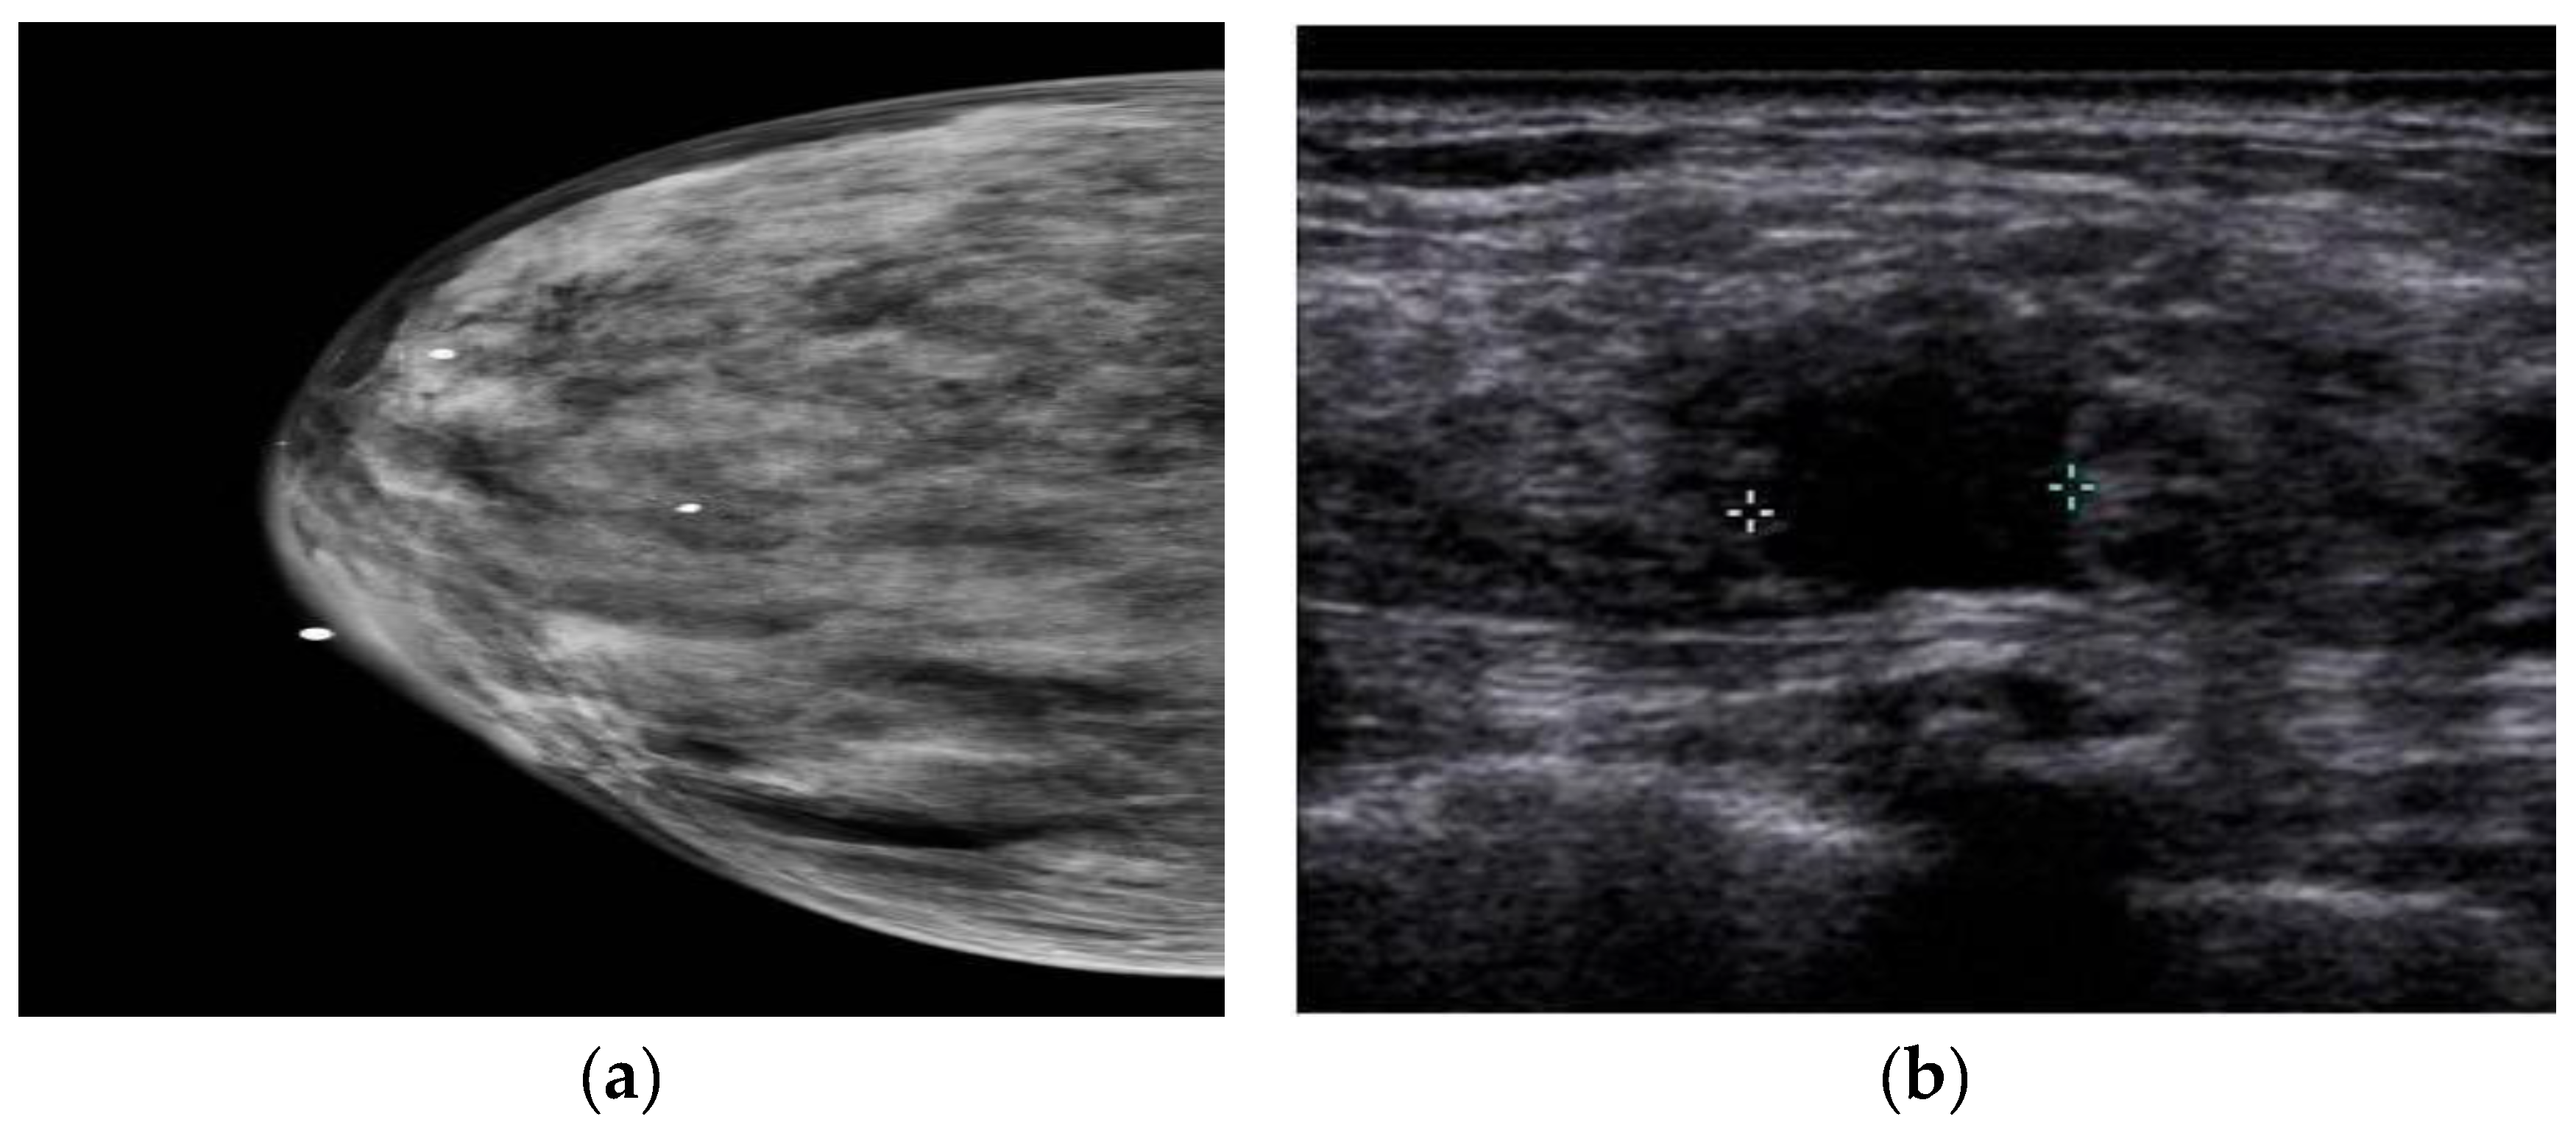

3. Ultrasound imaging (US)

- Choudhery, S.; Axmacher, J.; Conners, A.L.; Geske, J.; Brandt, K. Masses in the era of screening tomosynthesis: Is diagnostic ultrasound sufficient? The British Journal of Radiology 2019, 92, 20180801. [Google Scholar] [CrossRef]

- Vourtsis, A.; Kachulis, A. The performance of 3D ABUS versus HHUS in the visualisation and BI-RADS characterisation of breast lesions in a large cohort of 1,886 women. European Radiology 2018, 28, 592–601. [Google Scholar] [CrossRef]

- Sood, R.; Rositch, A.F.; Shakoor, D.; Ambinder, E.; Pool, K.-L.; Pollack, E.; Mollura, D.J.; Mullen, L.A.; Harvey, S.C. Ultrasound for breast cancer detection globally: a systematic review and meta-analysis. Journal of global oncology 2019, 5, 1–17. [Google Scholar] [CrossRef] [PubMed]

- Badu-Peprah, A.; Adu-Sarkodie, Y. Accuracy of clinical diagnosis, mammography and ultrasonography in preoperative assessment of breast cancer. Ghana medical journal 2018, 52, 133–139. [Google Scholar] [CrossRef]

- Harada-Shoji, N.; Suzuki, A.; Ishida, T.; Zheng, Y.-F.; Narikawa-Shiono, Y.; Sato-Tadano, A.; Ohta, R.; Ohuchi, N. Evaluation of adjunctive ultrasonography for breast cancer detection among women aged 40-49 years with varying breast density undergoing screening mammography: a secondary analysis of a randomized clinical trial. JAMA network open 2021, 4, e2121505–e2121505. [Google Scholar] [CrossRef] [PubMed]

- Thigpen, D.; Kappler, A.; Brem, R. The Role of Ultrasound in Screening Dense Breasts—A Review of the Literature and Practical Solutions for Implementation. Diagnostics 2018, 8, 20. [Google Scholar] [CrossRef]

- Iranmakani, S.; Mortezazadeh, T.; Sajadian, F.; Ghaziani, M.F.; Ghafari, A.; Khezerloo, D.; Musa, A.E. A review of various modalities in breast imaging: technical aspects and clinical outcomes. Egyptian Journal of Radiology and Nuclear Medicine 2020, 51, 57. [Google Scholar] [CrossRef]